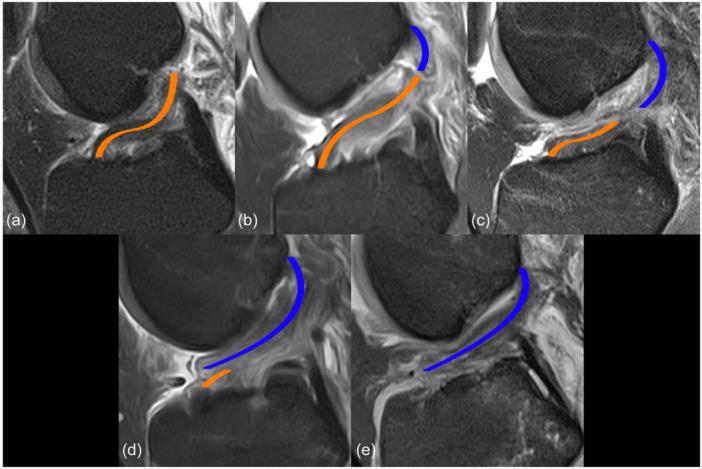

METHODS

A retrospective analysis of 446 consecutive patients with acute non-contact ACL injury was performed. Only patients with complete ACL tears verified during subsequent arthroscopy were included. Magnetic resonance imaging (MRI) was used to classify BB location, BB depth, ACL tear location and concomitant injuries (medial/lateral meniscus and medial/lateral collateral ligament). Demographic characteristics included age, gender, body mass index (BMI), type of sport and time between injury and MRI. Multiple linear regression analysis was used to identify independent predictors of ACL tear location.

One hundred and fifty-eight skeletally mature patients met the inclusion criteria. The presence of BB in the lateral tibial plateau was associated with a more distal ACL tear location ( = -0.27,  < 0.001). Less BB depth in the lateral femoral condyle showed a tendency towards more proximal ACL tears ( = -0.14;  = 0.054). Older age predicted a more proximal ACL tear location ( = 0.31,  < 0.001). No significant relationship was found between ACL tear location and gender, BMI, type of sport, concomitant injuries and time between injury and MRI.

不同的损伤机制是否会导致前交叉韧带(ACL)撕裂部位不同尚不清楚。本研究旨在分析骨挫伤(BB)的分布或深度与ACL撕裂部位之间的关系。

方法

结果